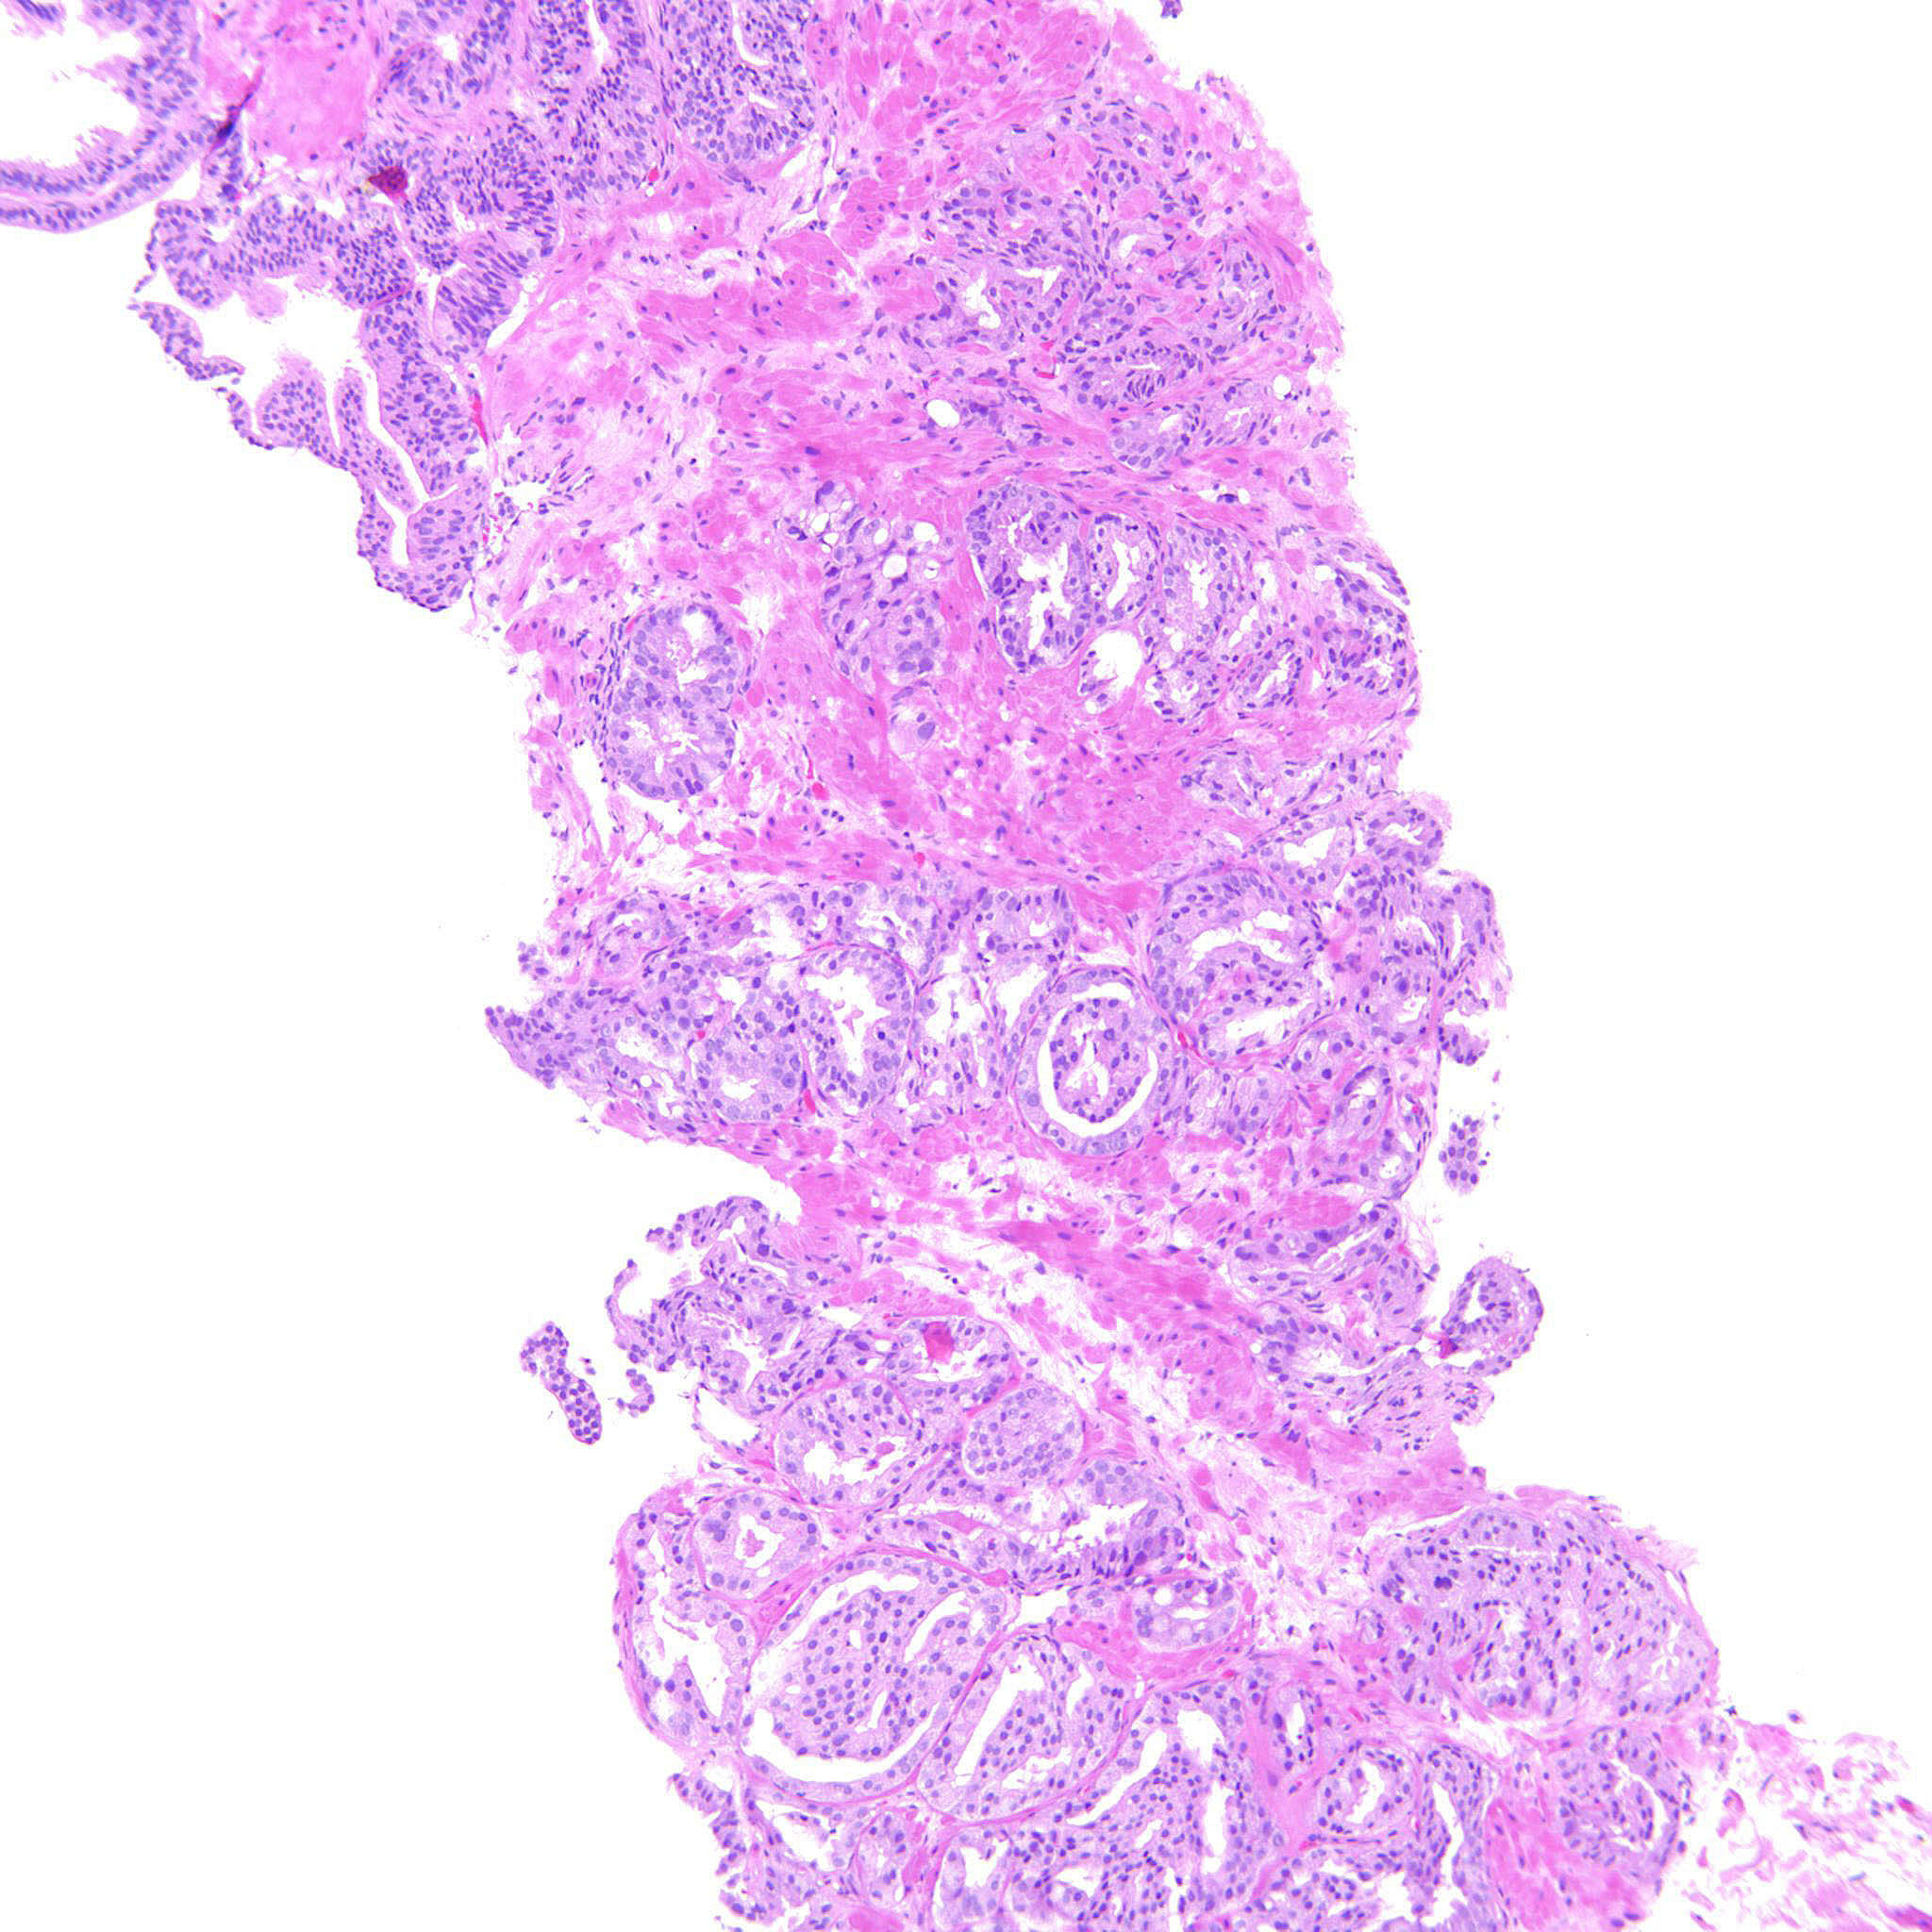

Consensus grade: GS 4+3=7 (ISUP 3)

Show diagnosis by expert panel members| User | Diagnosis | Difficulty | Comment |

|---|---|---|---|

| Pathologist 1 | GS 4+3=7 (ISUP 3) | Typical | |

| Pathologist 2 | GS 3+4=7 (ISUP 2) | Borderline higher | |

| Pathologist 3 | GS 3+4=7 (ISUP 2) | Typical | |

| Pathologist 4 | GS 4+3=7 (ISUP 3) | Borderline higher | |

| Pathologist 5 | GS 3+4=7 (ISUP 2) | Typical | |

| Pathologist 6 | GS 4+3=7 (ISUP 3) | Typical | |

| Pathologist 7 | GS 3+4=7 (ISUP 2) | Borderline higher |

Possible single cells but I favored them to be part of fused glands |

| Pathologist 8 | GS 3+4=7 (ISUP 2) | Borderline higher | |

| Pathologist 9 | GS 4+3=7 (ISUP 3) | Typical | |

| Pathologist 10 | GS 4+3=7 (ISUP 3) | Typical |

Approx. 80% pattern 4. Some glomerulations present. |

| Pathologist 11 | GS 3+4=7 (ISUP 2) | Borderline higher |

these cribriform glands are considered G4 |

| Pathologist 12 | GS 4+3=7 (ISUP 3) | Typical | |

| Pathologist 13 | GS 4+3=7 (ISUP 3) | Typical | |

| Pathologist 14 | GS 4+3=7 (ISUP 3) | Typical | |

| Pathologist 15 | GS 4+3=7 (ISUP 3) | Typical | |

| Pathologist 16 | GS 4+3=7 (ISUP 3) | Typical | |

| Pathologist 17 | GS 4+3=7 (ISUP 3) | Typical | |

| Pathologist 18 | GS 4+3=7 (ISUP 3) | Typical | |

| Pathologist 19 | GS 3+4=7 (ISUP 2) | Typical | |

| Pathologist 20 | GS 3+4=7 (ISUP 2) | Typical |

4+3 could also be an option, but I think thereis more 3 than 4 |

| Pathologist 21 | GS 4+3=7 (ISUP 3) | Typical | |

| Pathologist 22 | GS 4+3=7 (ISUP 3) | Typical | |

| Pathologist 23 | GS 4+3=7 (ISUP 3) | Typical | |

| Pathologist 24 | GS 4+3=7 (ISUP 3) | Borderline lower |

Case description (by case creator):

Gleason pattern 4 with glomeruloid bodies. There is also a GP 3 component.